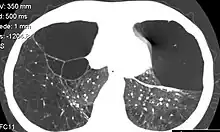

Individuals with A1AD may develop emphysema,[1] or chronic obstructive pulmonary disease during their thirties or forties even without a history of smoking, though smoking greatly increases the risk.[7] Symptoms may include shortness of breath (on exertion and later at rest), wheezing, and sputum production. Symptoms may resemble recurrent respiratory infections or asthma.[8]

A1AT is a glycoprotein mainly produced in the liver by hepatocytes,[9] and, in some quantity, by enterocytes, monocytes, and macrophages.[12] In a healthy lung, it functions as an inhibitor against neutrophil elastase,[13] a neutral serine protease that controls lung elastolytic activity which stimulates mucus secretion and CXCL8 release from epithelial cells that perpetuate the inflammatory state.[14] With A1AT deficiency, neutrophil elastase can disrupt elastin and components of the alveolar wall of the lung that may lead to emphysema, and hypersecretion of mucus that can develop into chronic bronchitis.[15] Both conditions are the makeup of chronic obstructive pulmonary disease (COPD).[16]

Normal blood levels of alpha-1 antitrypsin may vary with analytical method but are typically around 1.0-2.7 g/L.[17] In individuals with PiSS, PiMZ and PiSZ genotypes, blood levels of A1AT are reduced to between 40 and 60% of normal levels; this is usually sufficient to protect the lungs from the effects of elastase in people who do not smoke. However, in individuals with the PiZZ genotype, A1AT levels are less than 15% of normal, and they are likely to develop panlobular emphysema at a young age. Cigarette smoke is especially harmful to individuals with A1AD.[7] In addition to increasing the inflammatory reaction in the airways, cigarette smoke directly inactivates alpha-1 antitrypsin by oxidizing essential methionine residues to sulfoxide forms, decreasing the enzyme activity by a factor of 2,000.